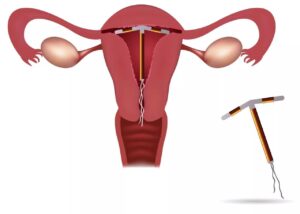

Đặt vòng tránh thai dạng (T) chứa đồng

Hiệu quả tránh thai cao lên tới 98%. Đây là một dụng cụ đặt trong tử cung, hoạt động dựa trên cơ chế ngăn cản quá trình thụ tinh và làm tổ của trứng Hạn sử dụng: Tối đa 10 năm